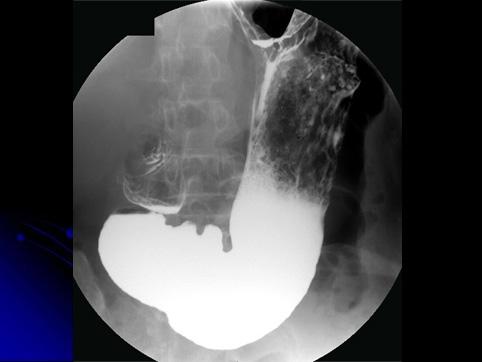

疾病(病理主体)的分类良性上皮性肿瘤/腺瘤

部位(按器官分)胃(部位)/前庭

检查方法X线

肿瘤的肉眼分类0型(表在型)/IIa型(IIa)

肿瘤最大直径20~24

多发性肿瘤(同一器官)有(同时性)